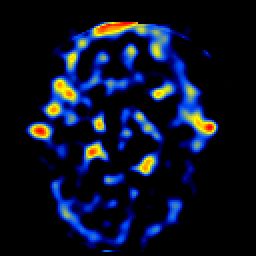

SPECT TL Study #5 -- Slice #25